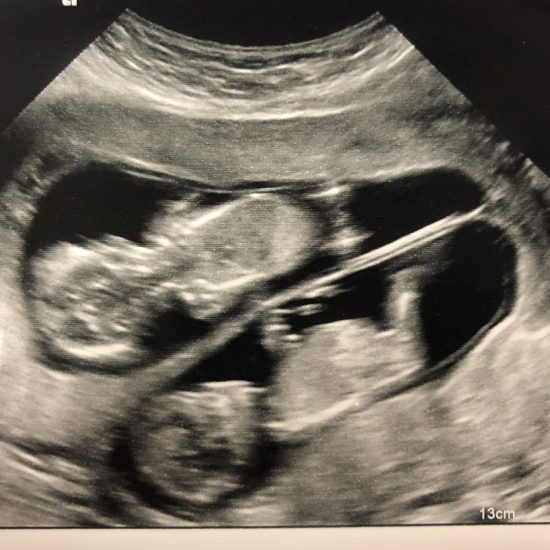

The babies’ heartbeats were monitored and I had a position scan, which showed a totally unexpected result. Both babies were now head down! I am almost certain that Twin 2 made his bid for exit whilst I was strapped to the monitor. The midwives wanted to crack on with things as soon as possible.